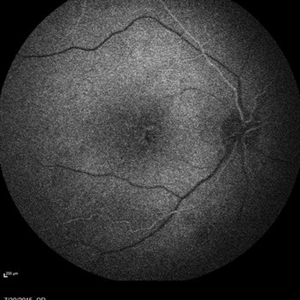

Retinal Dystrophy of 24-Year-Old Male/ IR OD

Nov 25 2015 by Zach Dupureur

Fluorescein angiography of a 24-year-old male. Juvenile retinoschisis on OCT. FA shows outer retinal staining. Could be associated with Goldman Farve Syndrome.

Photographer: Zach Dupureur OCT-C

Imaging device: Heidelberg Spectralis

Condition/keywords: Goldmann-Favre Syndrome, juvenile retinoschisis, retinal dystrophy